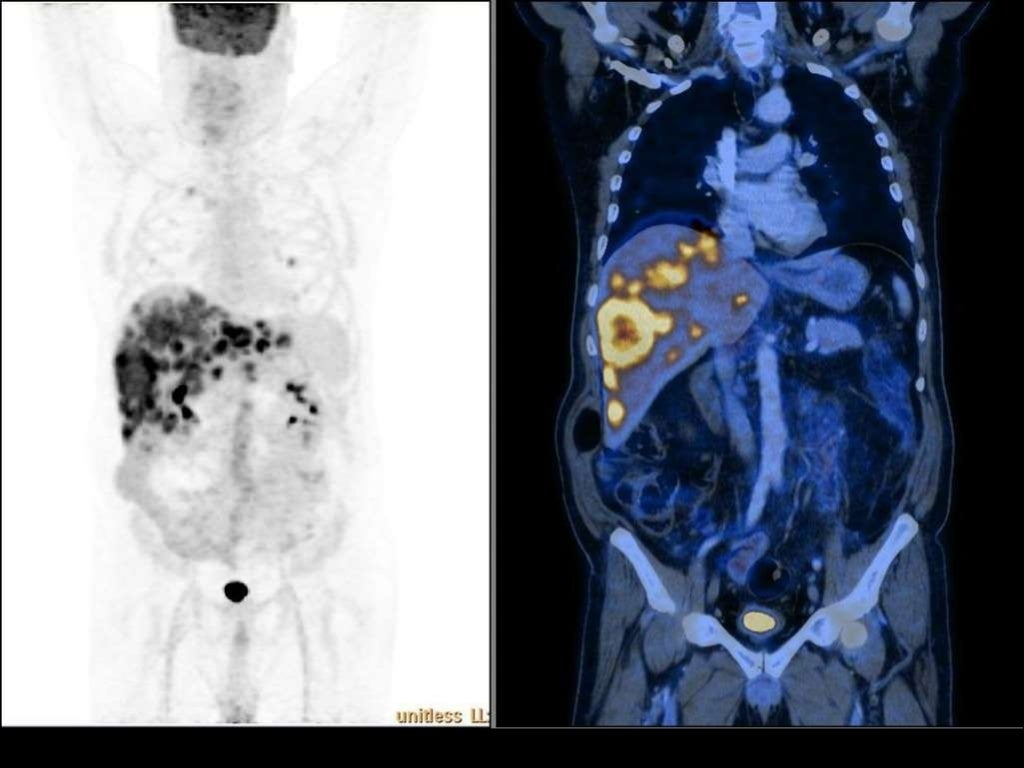

Гиперфиксация рфп при пэт кт

Гиперфиксация рфп при пэт кт 140 фото